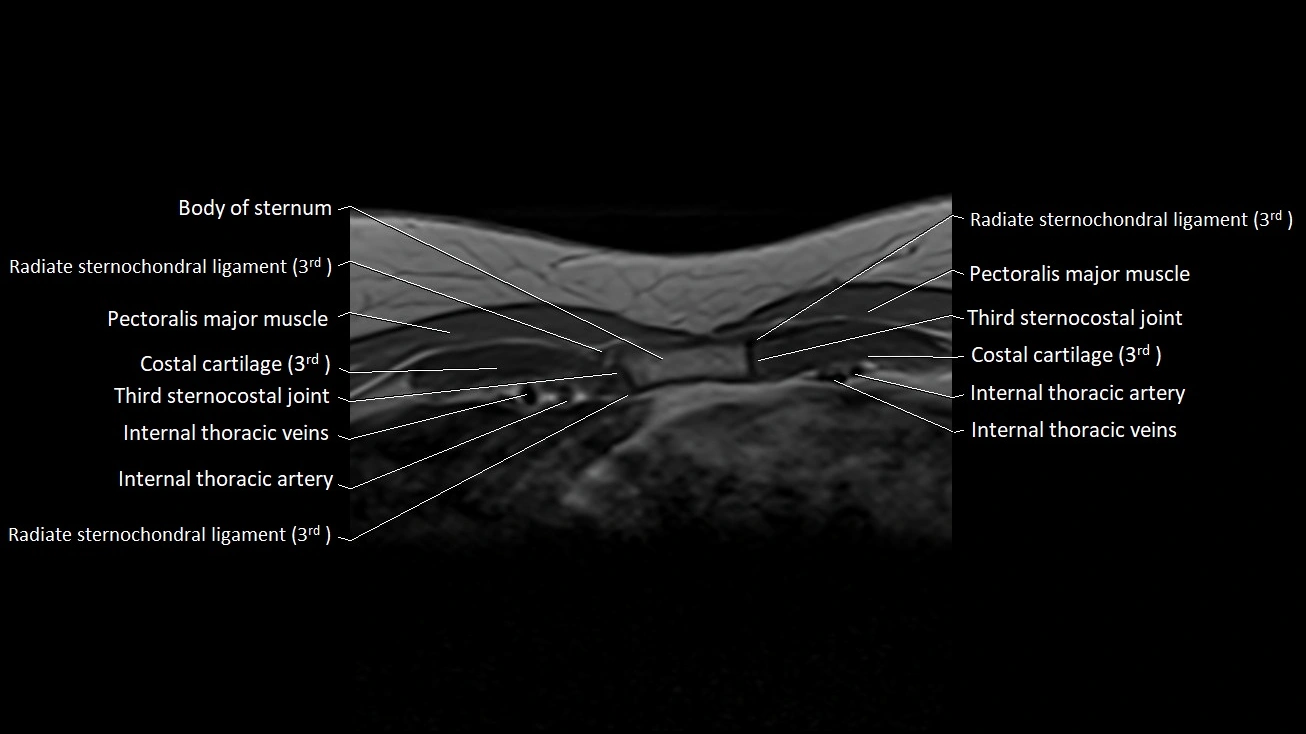

MRI images

image